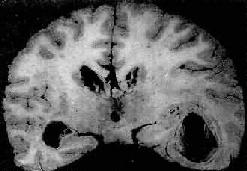

慢性脑脓肿

图16-12 慢性脑脓肿

右侧颞叶的脑脓肿与侧脑室相通